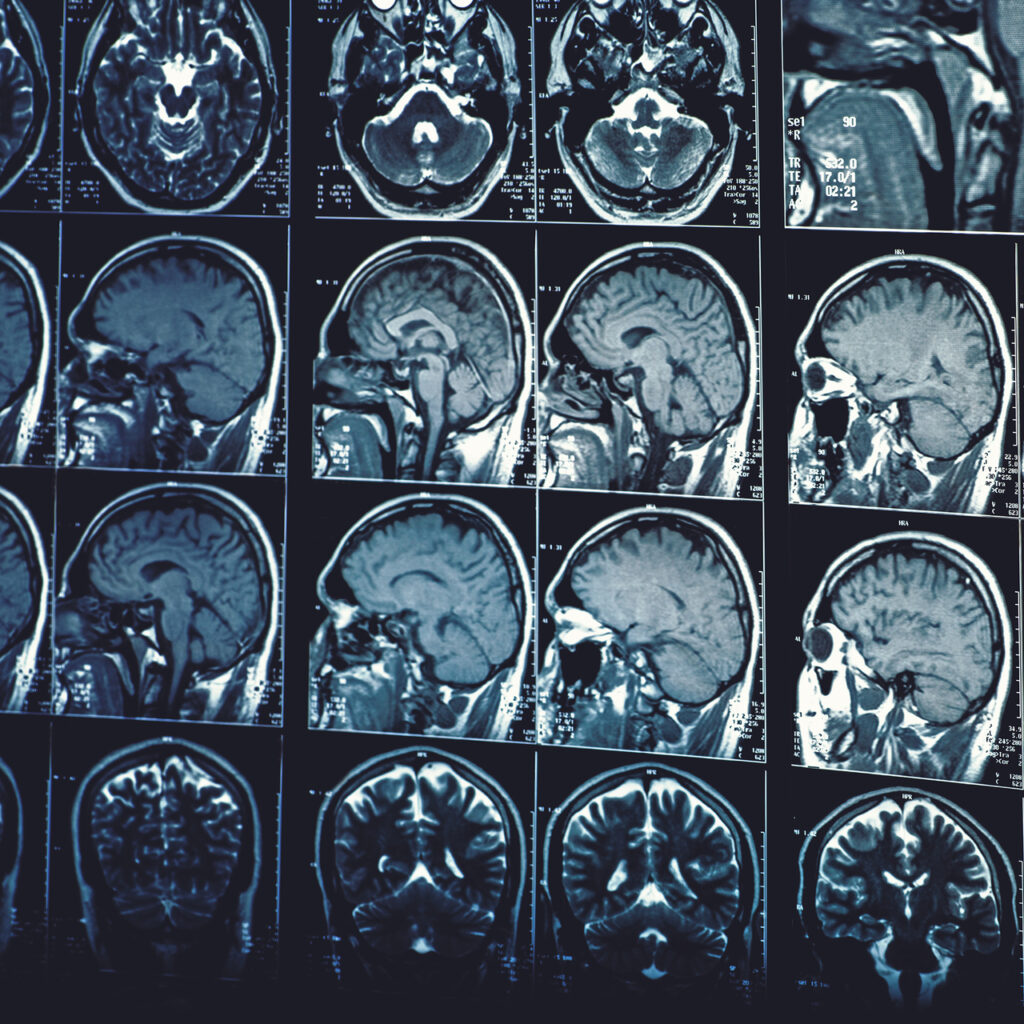

İstanbul’da bu yıl dördüncüsü düzenlenen ‘Mucize Organ Beyin Sempozyumu’, alanında uzman profesyonelleri ve inme geçirmiş ve hayata tutunmuş hastaları bir araya getirdi. İnme ve beyin hasarı yaşayan hastalar yeni bir hayata başladı ve bu yolculuk sürecini sempozyumda anlattı. İnmede acil müdahalenin önemi, inme belirtilerinin tanınması ve inme sonrası erken dönemde başlanan fizik tedavi programlarının ve robotik rehabilitasyonun hastanın normal hayatına dönmesindeki başarısına dikkat çekilen toplantıda, beyin hasarı ve beyin tümörü sonrası nöro-rehabilitasyon programlarının önemi hakkında değerli bilgiler aktarıldı. İnme ve beyin hasarı nedeniyle sakatlık ve ölüm riski ile karşı karşıya kalan ancak doğru tedavi planlaması sayesinde yeniden hayata dönen hastalar bu süreçteki ilham verici hikayelerini dinleyicilerle paylaştı.

Bu sempozyumu beyin hasarında farkındalık yaratmak için yaptıklarını vurgulayan Prof. Dr. Engin Çakar, “Beyin hasarı, inme ve travmatik beyin hasarlarını ön planda tutan, tüm beyin hasarlarını kapsayan konular hakkında bilgilendirici bir sempozyum. Bu sempozyum ile farkındalığı artırmayı amaçladık. İnme ile karşılaşma oranı dünyada çok yüksek bir rakama sahip. Her yıl 15 milyon kişi inme geçiriyor. Her 4 insandan biri hayatı boyunca en az bir kez beyindeki damar ile ilgili problem le karşılaşıyor. Toplumdaki en büyük 2 veya 4’üncü ölüm nedeni olan ve yetişkin özürlünün en büyük nedeni olan inmeye dair farkındalığı artırmak ve önlemek için bu toplantıları yapıyoruz. Biz bu sempozyumda hastalığın bilimsel tarafını anlatıyoruz. Konusunda uzman doktorlar ise kendi yaptığı profesyonel uygulamaları anlatıyor. Hastalığı yaşamış kişiler de bu süreci nasıl atlatacaklarını anlatıyorlar. İnmelerin yüzde 80’i önlenebilir. Lütfen hayatınıza dair tedbirler alın. Tedavilerinizi düzgün yaptırın ve bu hastalığı yaşamayın, yaşamanın bedeli çok ağır olabiliyor. Travmatik beyin hasarı da dünyada çok fazla görülüyor ve bugün bu konuya da dikkat çekmek istiyoruz” dedi

İnme yaşayan hastalardan Neşet İsmet Behzetoğlu ile toplantıya katılan babası Hakan Behzetoğlu, oğlunun yaşadığı olayı nazar olarak değerlendirerek, şunları söyledi: “Oğlum 2022 Eylül’de bu olayı yaşadı. Oğlumla işte, oturuyorduk. Karşı karşıyayken, hiçbir şey yokken ummadığımız bir anda bu hastalığı yaşadı. Hastalığına avm deniyor. Beyninde bir baloncuk oluşmuş. Şimdiye dek de hiçbir film çektirmemiştik, bu nedenle tabii ki fark edemedik. Bu olay yaşandıktan sonra sürecimiz başladı. İlk önce İskenderun’da beyin kanaması sebebiyle bir ameliyat geçirdi. 15 gün ardından İstanbul’a naklimiz gerçekleşti. 2,5 ay başka bir hastanede kaldı, ardından Şişli’deki bir hastaneye geldik. Sürecimiz orada hala devam ediyor. Kardeşim radyolog ama o da şimdiye dek oğluma film çekmemişti. Eğer film çekmiş olsaydık, oğlumun hastalığını görebilirdik. İnsanlara verebileceğim en büyük tavsiye, her yıl düzenli olarak film çektirmeleri. Oğlum hiçbir şeyi fark etmiyordu ve anlamıyordu. Buraya geldikten sonra 2 yıllık süre zarfında çok yol katettik. Engin Hoca ve ekibi sayesinde oğlum çok iyi. Allah hepsinden razı olsun.